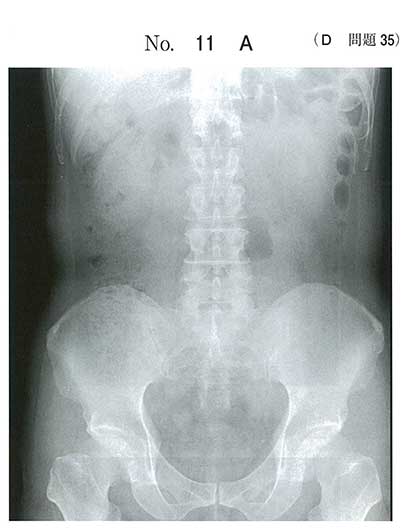

難しいけどx線透過性が低いと考えa

尿酸高いし、レントゲンでうつらないから単純にa

x線陰性結石なので尿酸ですね

尿路結石で一番多いのはシュウ酸カルシウムです

リン酸アンモニウムマグネシウムは感染結石でサンゴ状結石に多いです